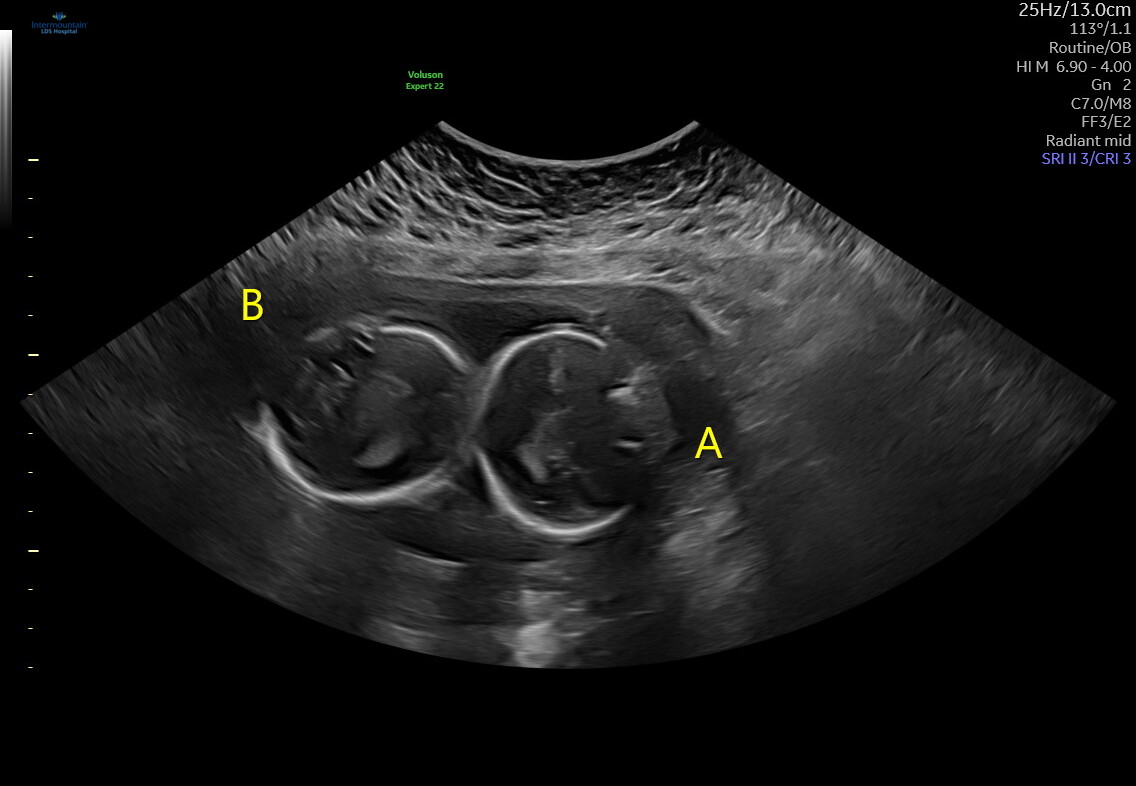

πΆπ Twin Baby Reveal ππΆ

Guess Baby A

Boy

Girl

Guess Baby B

π It's Twin Girls! π

πDue May 23, 2026π